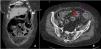

Fifteen months later, the patient experienced a spontaneous terminal ileal perforation, diagnosed by CT (Fig. 1), complicated by faecal peritonitis and bacteraemia (Bacteroides fragilis). The clinical presentation included vomiting and acute abdominal pain with elevated CRP. Ileal resection with lateral-lateral anastomosis was performed with subsequent conversion to terminal ileostomy due to anastomotic dehiscence and favourable postoperative recovery. Histopathological analysis revealed inflammation, vascular congestion, and fibrosis in the ileal wall without evidence of malignancy. Sarilumab was discontinued before surgery and colchicine was restarted, with no further flares for 18 months. However, the patient subsequently progressed to rheumatoid arthritis (RA) and was started on MTX and low-dose glucocorticoids (GC). From that time to the present, and over a follow-up period of 2 years, the patient has remained clinically asymptomatic, with no new episodes of abdominal pain.

Extensive diffuse pneumoperitoneum associated with a significant amount of free fluid predominantly in left parietocolic gutters (white arrow). In the distal ileum (approximately 10–15 cm from the ileocecal valve) there is a 5 mm parietal solution of continuity, suggestive of perforation (red arrow).